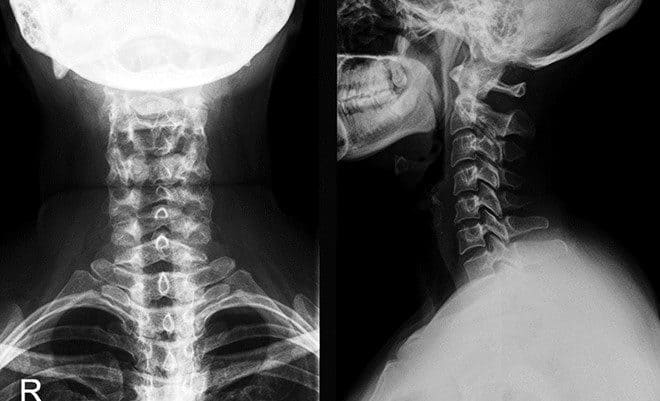

Рентгенография шейного отдела позвоночника в 2-х проекциях (со снимком)

Рентгенологический метод диагностики травм и заболеваний в области шеи.

Исследование делается обычно в двух проекциях: боковой и передней (прямой). От пациента требуется в определенные моменты сохранять строгую неподвижность. Перед процедурой следует раздеться до пояса и снять все украшения с исследуемой области тела (в первую очередь металлические предметы).